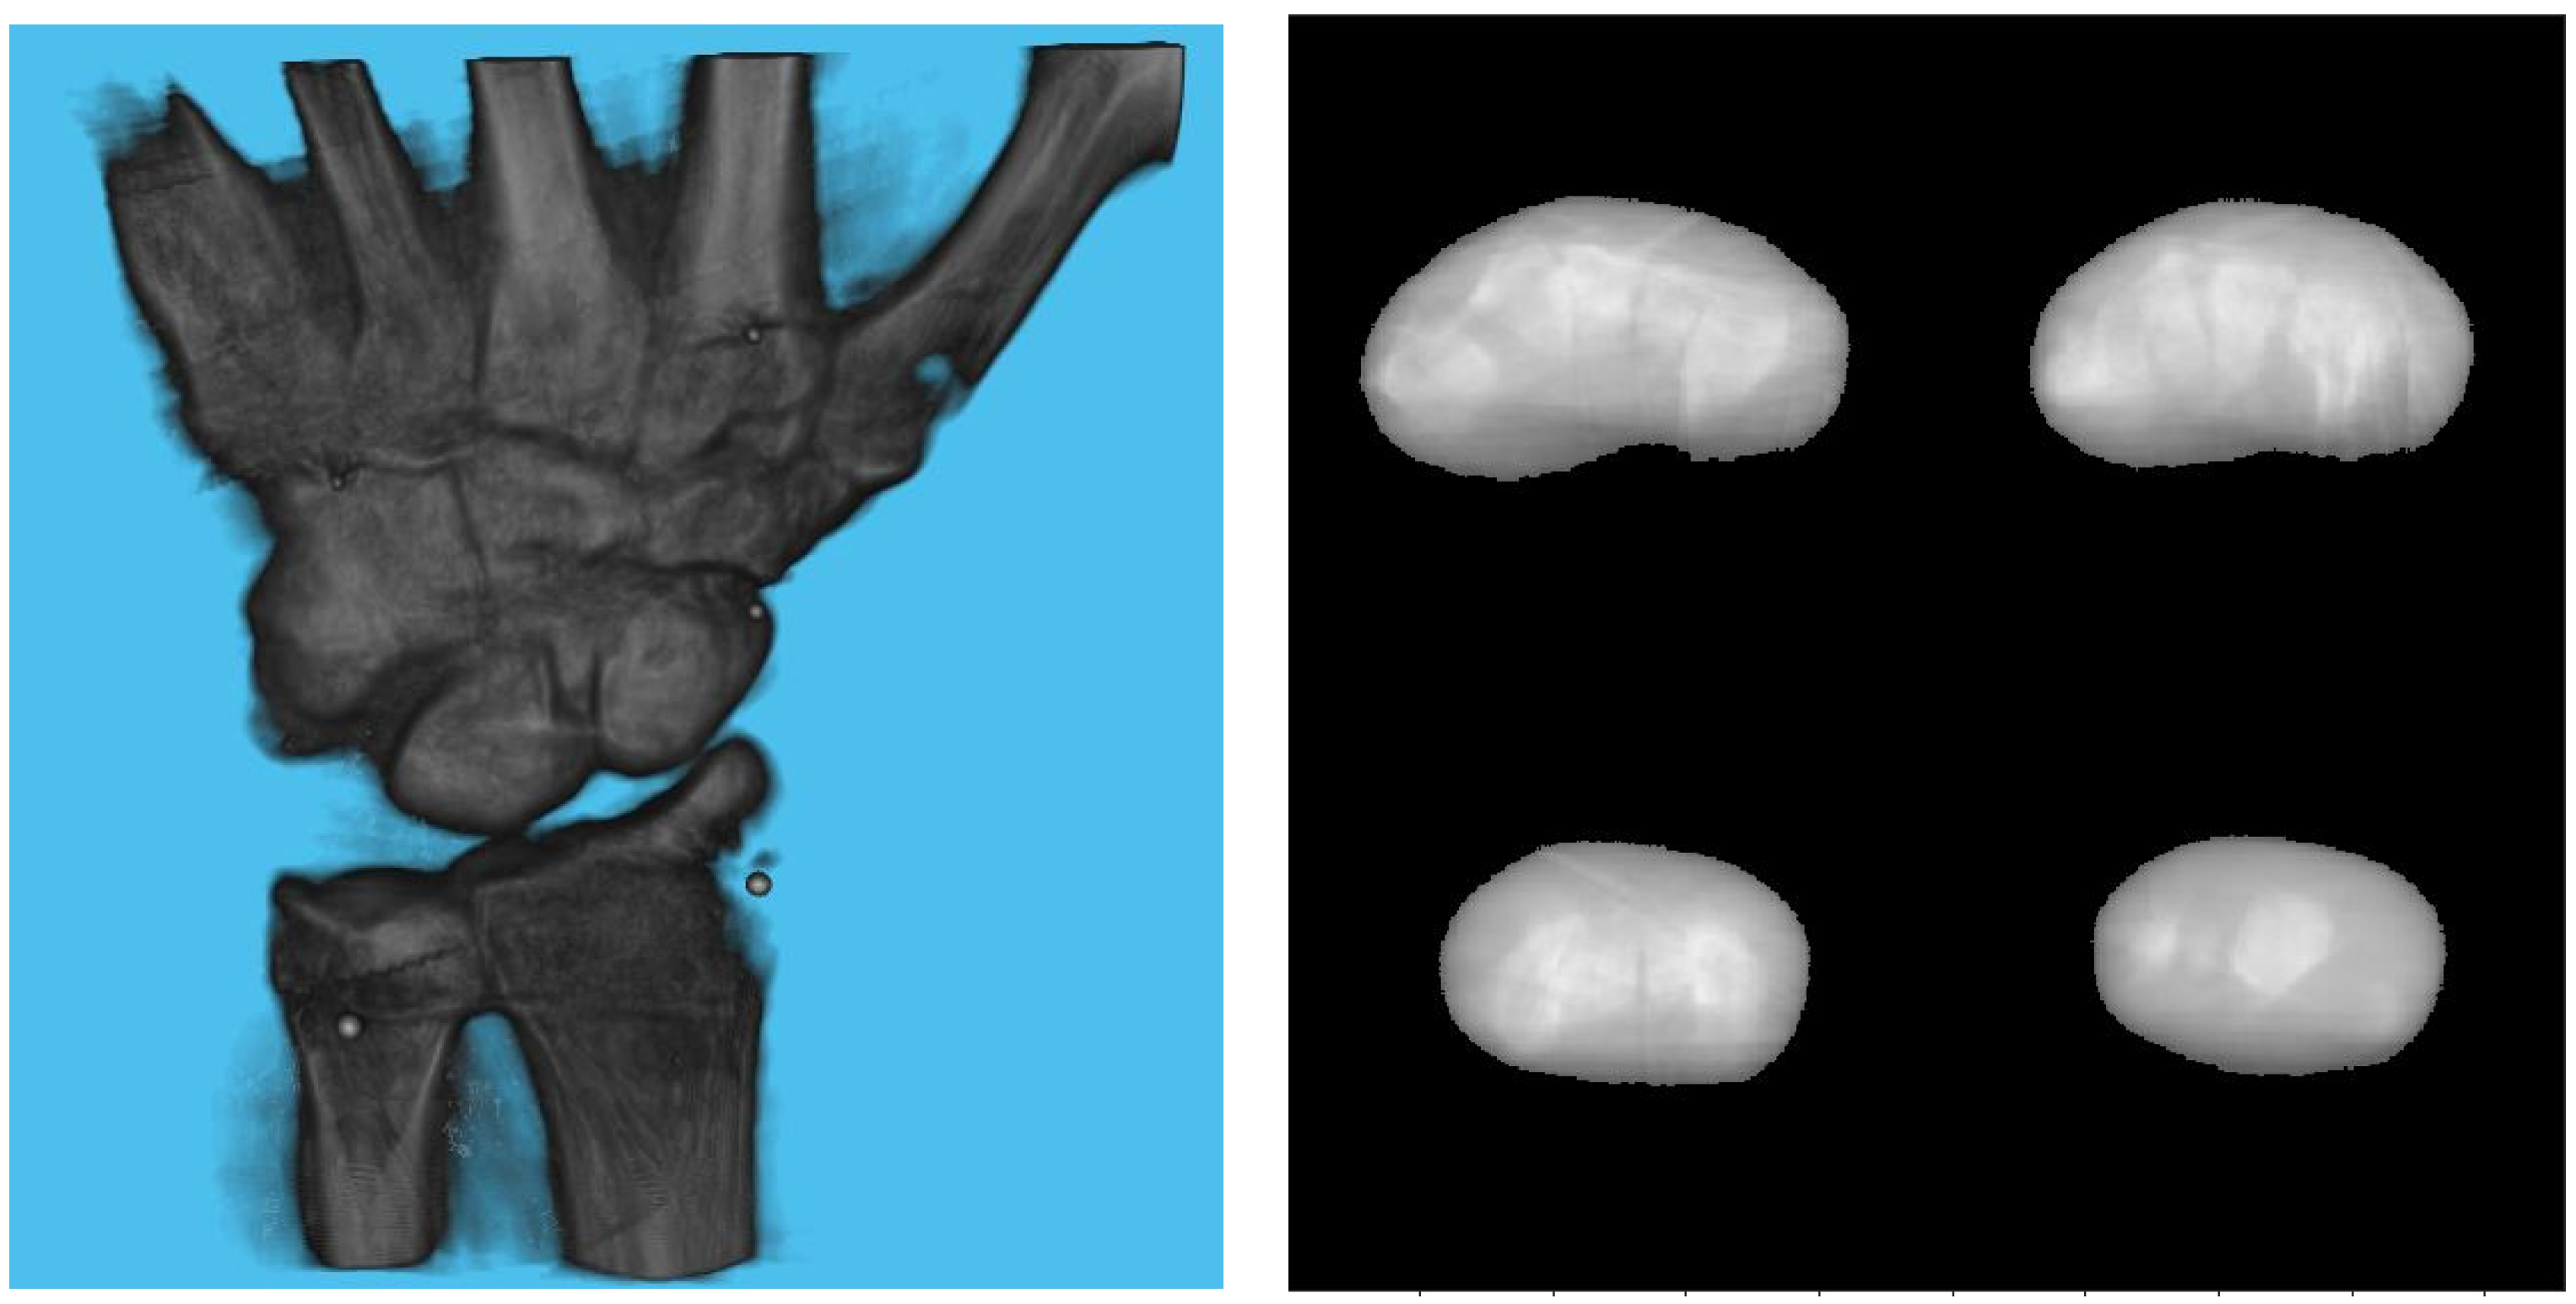

3. Experiments and Results

3.1. Simulation Setup

3.2. Effect of Board Thicknesses and Marker Sizes on Reconstructed Image Quality